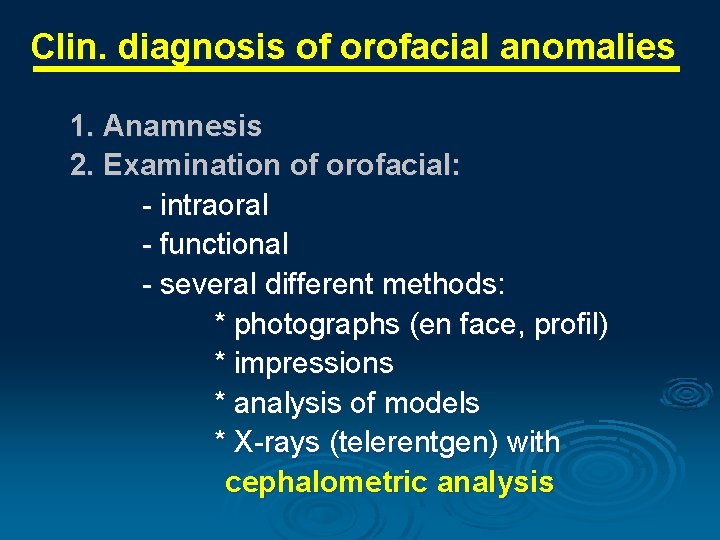

Clin. diagnosis of orofacial anomalies 1. Anamnesis 2. Examination of orofacial: - intraoral - functional - several different methods: * photographs (en face, profil) * impressions * analysis of models * X-rays (telerentgen) with cephalometric analysis